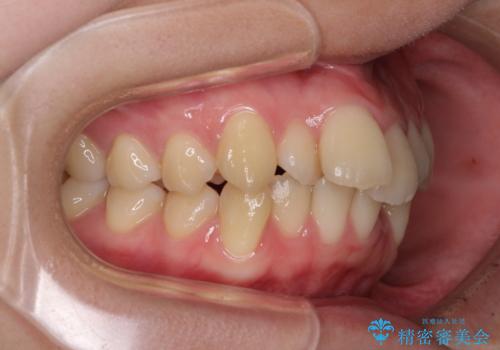

- 前歯のデコボコと突出感を気にして来院された患者様です。

上下左右第一小臼歯4本を抜歯して、積極的に口元を引っ込めるよう、ワイヤー装置にて矯正治療を行うこととしました。

口の閉じにくさが改善され、横顔のシルエットも大幅に改善されました。